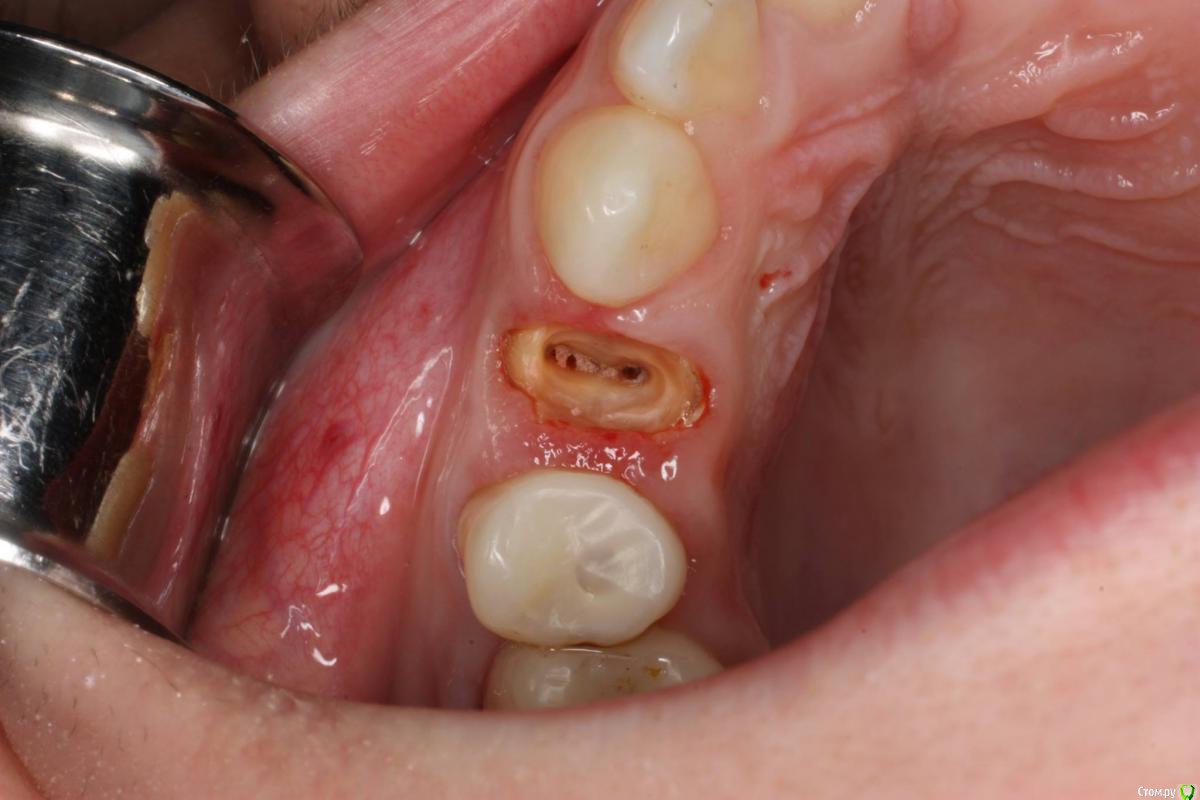

togrul Опубликовано 24 ноября, 2016 Поделиться Опубликовано 24 ноября, 2016 Имплантация проводилась 6 месяцев назад . Пациентка запротезирована. Это моя 2 имплантация была . 7 Ссылка на комментарий

togrul Опубликовано 24 ноября, 2016 Автор Поделиться Опубликовано 24 ноября, 2016 Нет Bio oss использовали . Ссылка на комментарий

syrovovec Опубликовано 24 ноября, 2016 Поделиться Опубликовано 24 ноября, 2016 Графт может и не особо нужен, а сст просится Ссылка на комментарий

АнтонТЛТ Опубликовано 24 ноября, 2016 Поделиться Опубликовано 24 ноября, 2016 Не вижу показаний для сст, коронкой на раз всё отожмётся 2 Ссылка на комментарий

togrul Опубликовано 24 ноября, 2016 Автор Поделиться Опубликовано 24 ноября, 2016 А вообще нужен в таких случаях графт или нет? Ссылка на комментарий

Maxfac Опубликовано 25 ноября, 2016 Поделиться Опубликовано 25 ноября, 2016 А вообще нужен в таких случаях графт или нет?А это интересный вопрос, который стоило бы обсудить отдельно. 1 Ссылка на комментарий